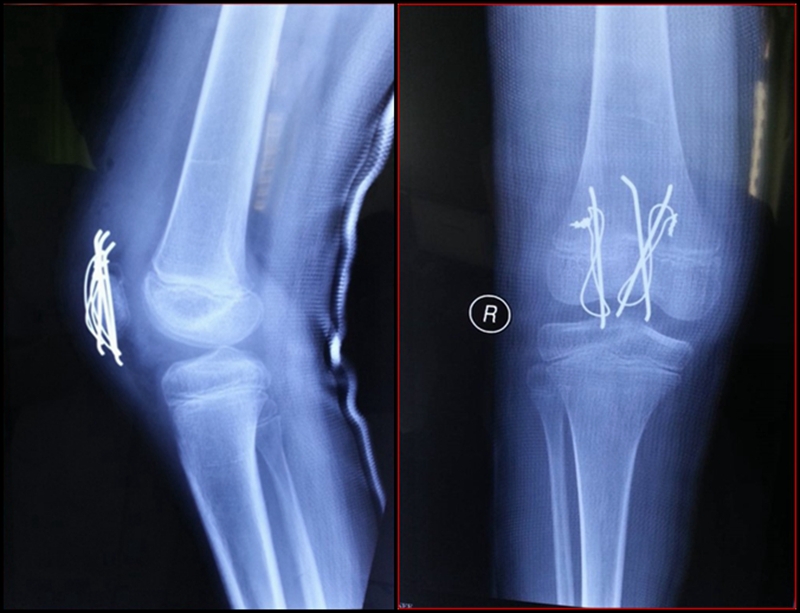

图3 受伤后3周MRI

考虑此患儿伤后已3周,组织全科讨论,确定诊断为:髌骨上极陈旧性套状撕脱骨折。充分与家属沟通远期预后。